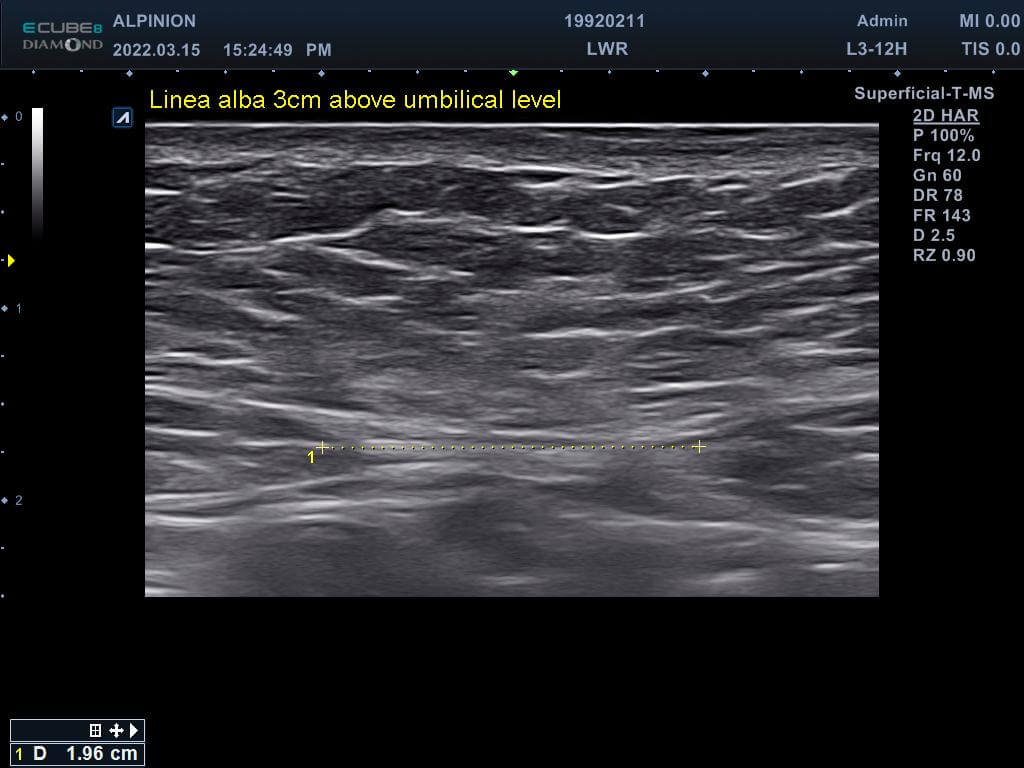

專業的醫師先在磁刺激前測量林小姐的腹直肌厚度,發現雙側的腹直肌分別為0.81cm(右側)與0.78cm(左側),同時雙側白線的距離也長達1.96cm,已經達到腹直肌分離的狀況。在使用了四周共8次的增肌減脂機後,雙側的腹直肌增厚為0.93cm(右側)與0.82cm(左側),同時雙側白線的距離減少1.46cm並明顯增厚,代表結締組織已經增生修復了。

使用(前)白線長度1.96cm